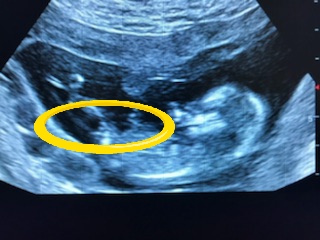

Djmommy I'm so very sorry [emoji22] I'm not an expert but I would've leant boy as I *think* I see stacking but again I'm no expert. Take care of yourself and big hugs xo.

Top pic shows a forked nub but not like girly forks I've seen, not to say that it isn't of course, just that I'm not familiar with them looking like that.